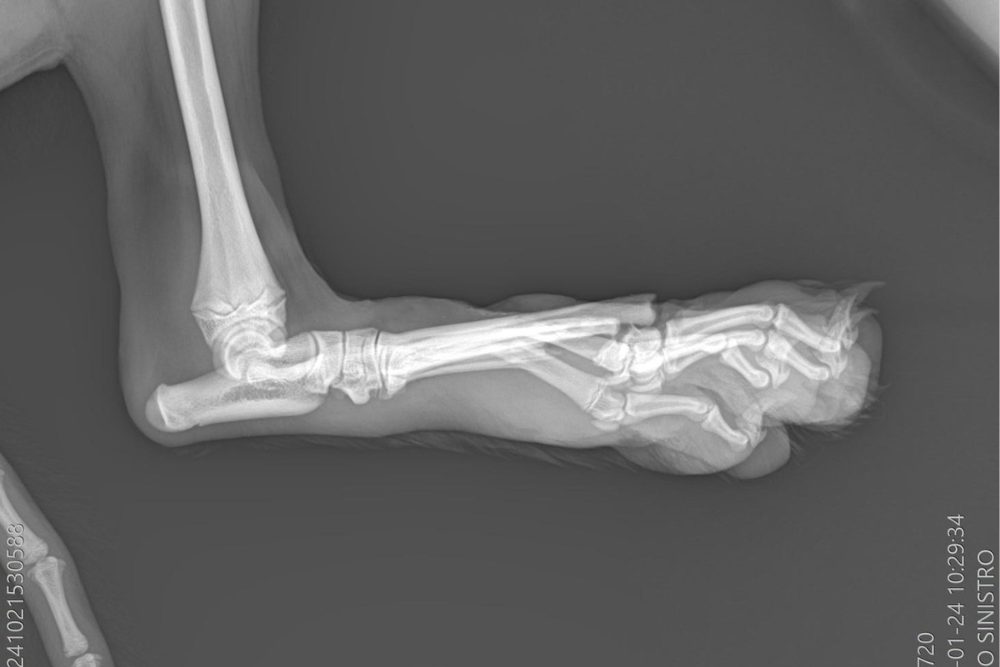

Im Canile Tortolì wurde Davide sofort erstversorgt und stabilisiert. Am nächsten Tag brachten Röntgenaufnahmen das ganze Ausmaß ans Licht: Seine Hinterpfoten waren verletzt, die linke besonders schwer, Knochen standen heraus. Der Anblick ließ uns befürchten, dass nur eine Amputation der rechten Hinterpfote bleiben würde.